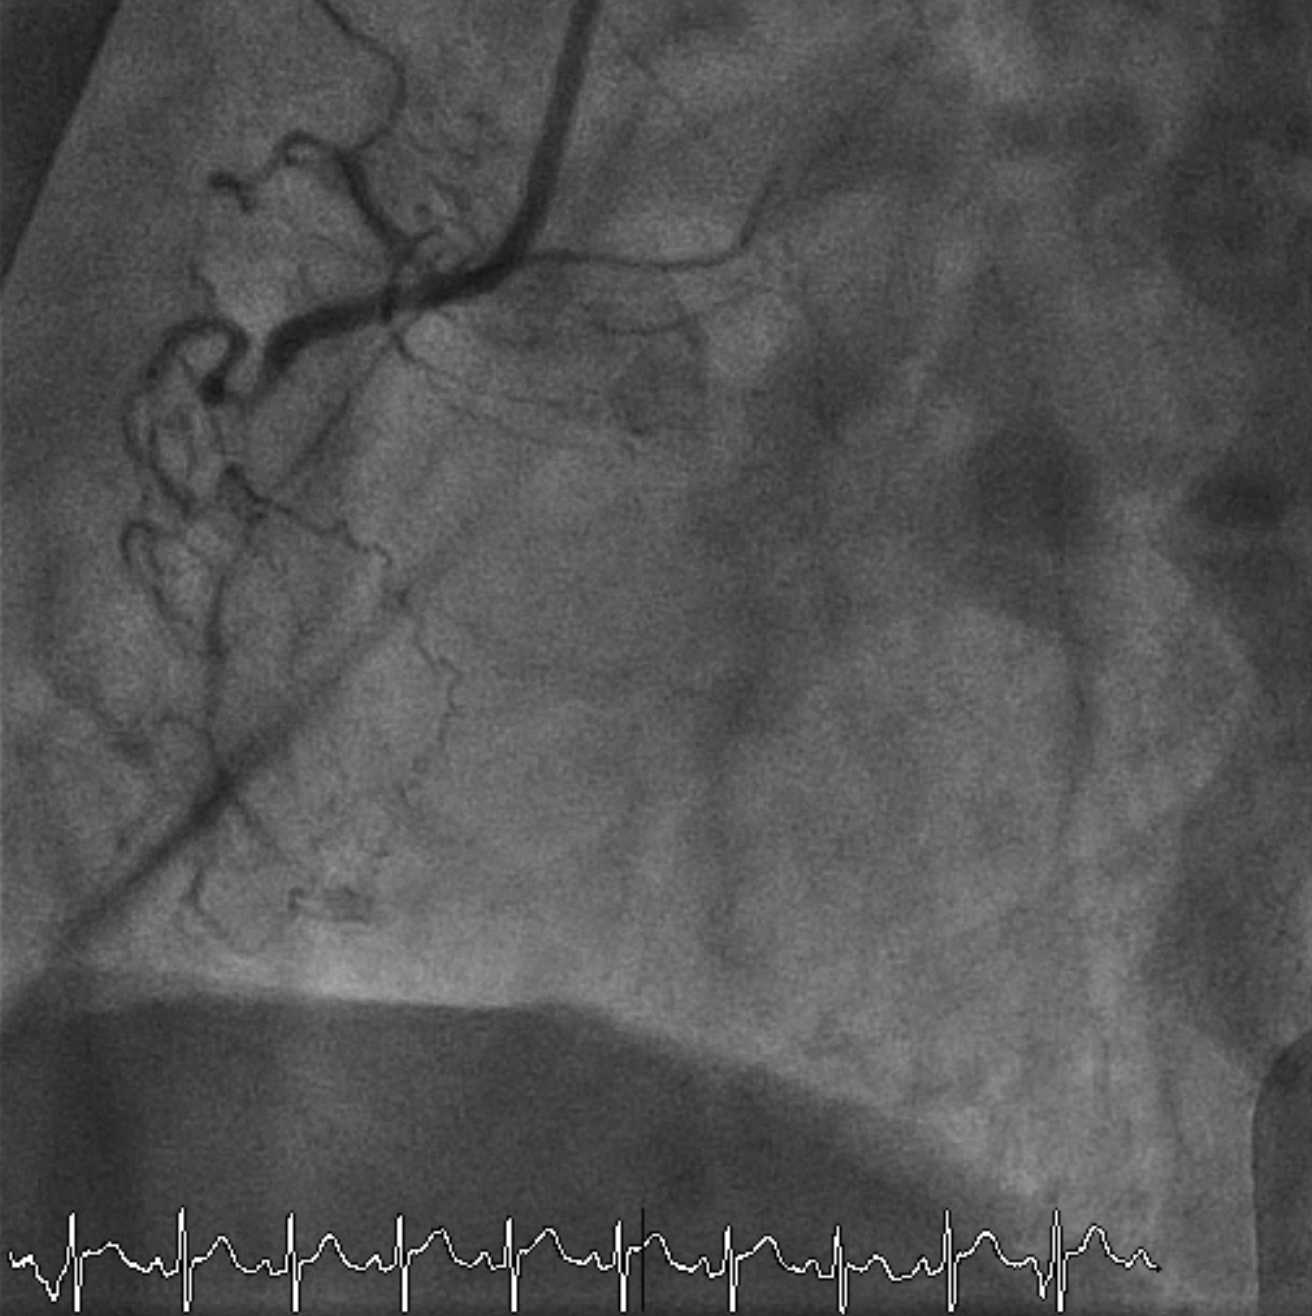

A 6 Fr JR 4.0 guiding catheter was engaged via femoral approach and JL 4 catheter was used for dual injection. We planned to perform PCI at proximal RCA CTO with antegrade wire escalation technique first. We successful wired to PL branch of RCA using microcatheter with Gaia Next 2 guidewire (Failed using Fielder XT). The microcatheter could not cross lesion. Try using CTO balloon 0.75/8 mm and 1.0/6 mm to pre-dilatation but still uncrossable. So we put the microcatheter farthest and successful bare wiring the RotaWire Floppy to PL. Rotational atherectomy was done with Burr 1.25 mm at 172,000 - 146,000 rpm total 4 runs. IVUS was pulled back from PL-RCA showed intra-plaque wiring, calcified nodules with cracked calcific plaques and reverberation. We prepared the lesion proximal to mid RCA lesion with non-compliant 2.5/15 mm balloon at 20 atm and scoring 3.0/13 mm balloon at 18-20 atm. A 3.0/38 mm stent could not be delivered the lesion. We used the guide extension catheter with balloon-assisted tracking techinque for delivery. The stent was successfully deployed to mid RCA. The 3.5/28 mm stent was deployed to proximal to mid RCA and 3.5/18 mm stent was deployed at ostial RCA. Post-dilatation with non-compliant 3.0/15 and 3.5/18 mm at 16 atm. Final angiogram showed good coronary blood flow and IVUS demonstrated well stent expansion, no malapposition and no stent edge dissection.